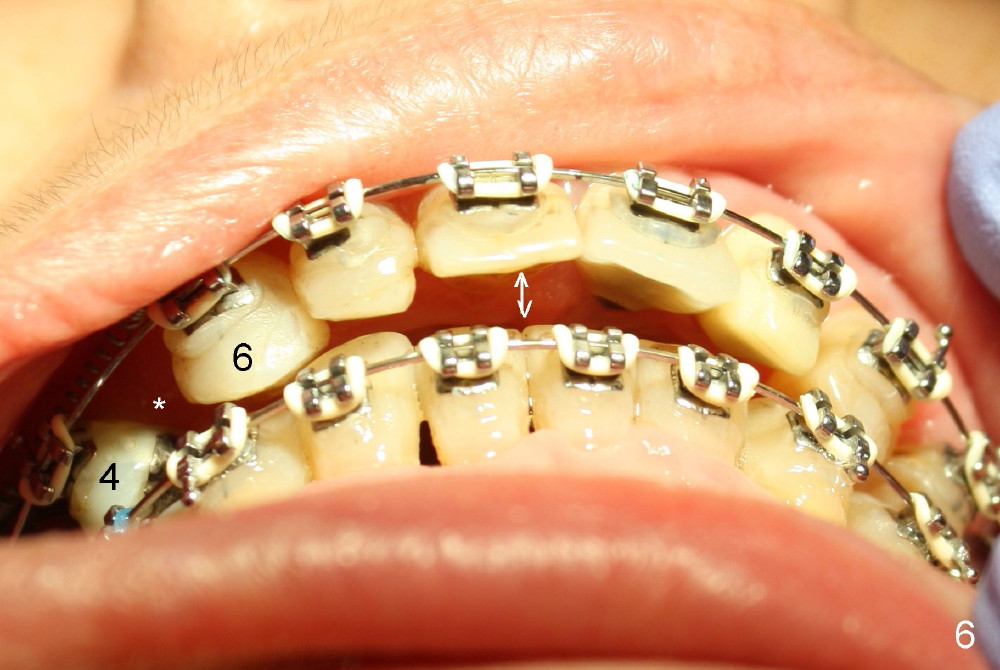

An abutment is placed; a provisional is fabricated, a premolar band is tried in and cemented (Fig.4: #30). Next visit, the implant will be used as an anchorage to distalize #29 and 28 (arrow) so that there is enough space to restore the distal defect of #27 (*).

The upper midline seems to be deviated to the left (Fig.5 dashed lines). There is large anterior overjet (Fig.6 double arrows). The space between #4 and 6 (Fig.6,7 *) is to be closed by a closed spring between.#3 and 6, whereas the space mesial to #30 (Fig.4) will be closed by power chain between #28 and 30 (Fig.7) so that the tooth #27 has space to rotate and the distolingual caries is to be excavated (*).